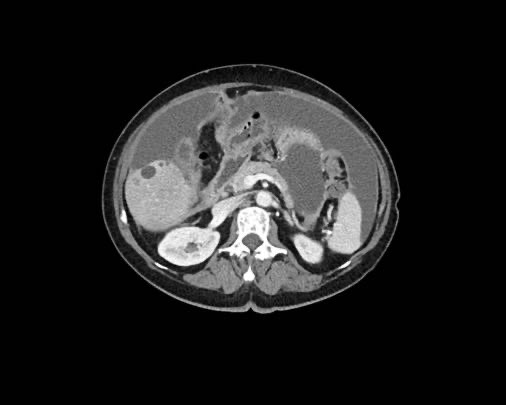

Ca lâm sàng 1

Cuộn qua các lát cắt.

Bạn có thể phát hiện tất cả các tổn thương cấy ghép phúc mạc không?

Bệnh nhân này đã được phẫu thuật và toàn bộ phúc mạc được ghi nhận phủ kín bởi các tổn thương u dạng kê.